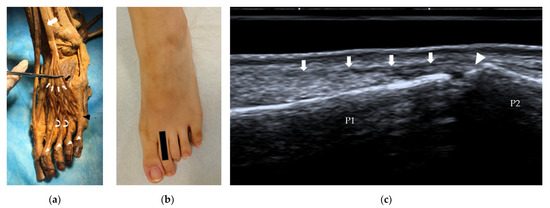

2. US Techniques and Methods

3.3. Soft Tissues between Metatarsal Bones

3.4. Sesamoids and Osseous Components

3.5. Ligaments and Joint Capsule